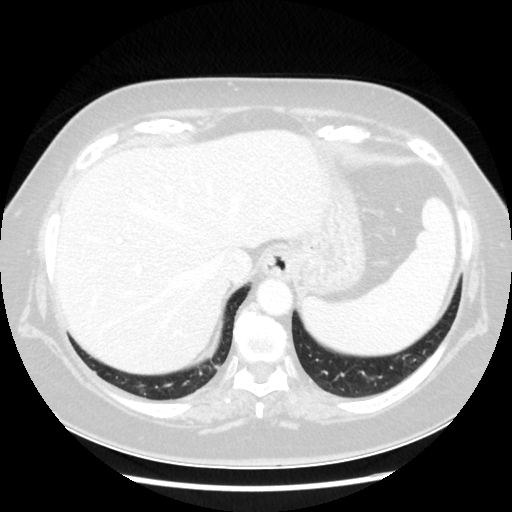

Original NATIVE CT scan (input)

Full window (WL 1023.5, WW 4095 β†’ Low βˆ’1024, High +3071)

Generated VENOUS CT scan (A→B translation)